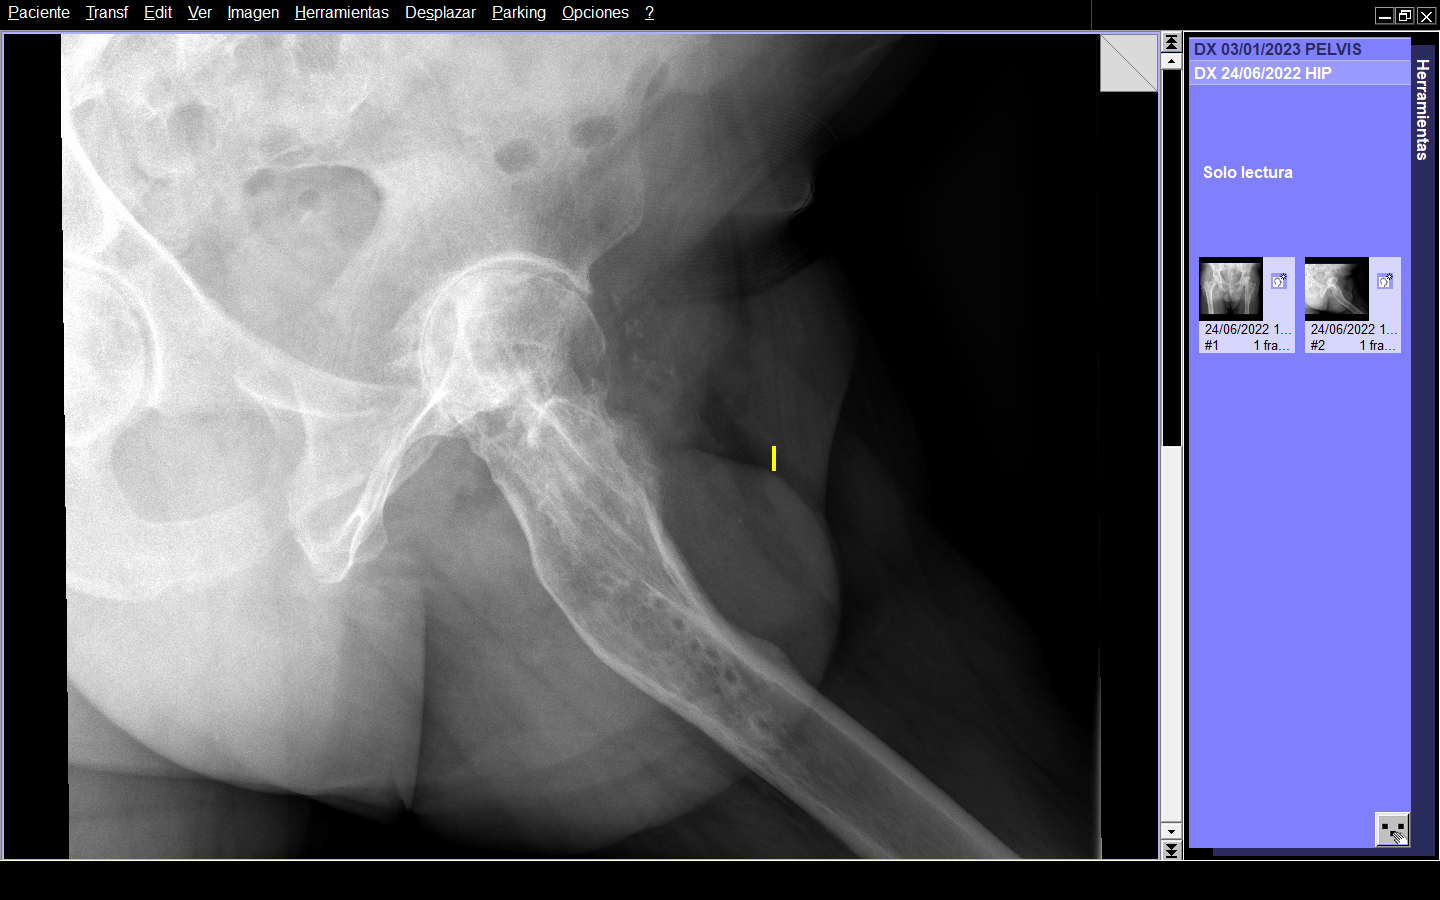

Radiográficamente, en AP presentaba deformidad en fémur proximal izquierdo de 160º en valgo, disminución del espacio articular, geodas en cabeza femoral. En la radiografía lateral se observaba curvatura en la metáfisis femoral con ápex posterior de 27º. (Figura 1 y 2)

Figura 1. Radiografía AP de ambas caderas.

Figura 2. Radiografía axial de cadera.